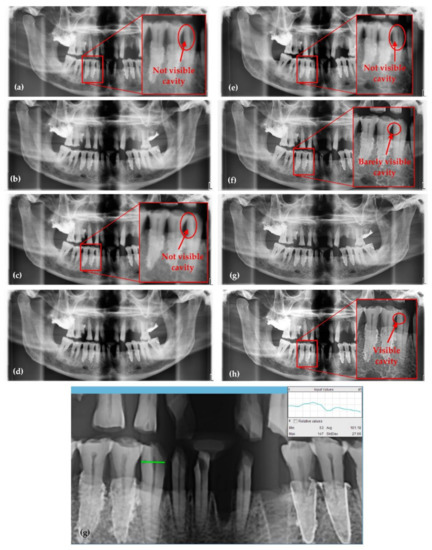

3.1. Optimized Protocol with OCT for X-ray Imaging Calibration. Panoramic Radiography

| Panoramic Radiographs (Figure 8) | Anode Voltage (kV) | Current Intensity (mA) | Exposure Time (s) | Radiation Dose (µSv) | ||

|---|---|---|---|---|---|---|

| a | 60 | 1 | 13.7 | 0.65 | 0.2 | 4.15 |

| b | 61 | 2 | 15 | 1.74 | 0.34 | 4.1 |

| c | 62 | 3.2 | 15 | 2.89 | 0.3 | 4 |

| d | 64 | 4 | 15 | 3.88 | 0.19 | 3.92 |

| e | 66 | 6.3 | 15 | 6.54 | 0.43 | 3.67 |

| f | 68 | 8 | 15 | 8.84 | 0.36 | 3.57 |

| g | 70 | 10 | 15 | 11.68 | 0.46 | 3.45 |

| h | 72 | 11 | 15 | 13.72 | 0.58 | 3.35 |

Panoramic Radiographs (Figure 8) | ||||||

| a | 3 | 3479 | 2104.47 | 1122.57 | 0.998 | 3.096 |

| b | 17 | 3377 | 2031.94 | 1094.54 | 0.989 | 3.069 |

| c | 20 | 3485 | 2012.62 | 1102.82 | 0.988 | 3.141 |

| d | 32 | 3317 | 1975.26 | 1060.52 | 0.980 | 3.097 |

| e | 31 | 3489 | 2106.08 | 1078.73 | 0.982 | 3.205 |

| f | 22 | 3456 | 2081.59 | 1056.53 | 0.987 | 3.250 |

| g | 70 | 3576 | 2172.58 | 1083.91 | 0.961 | 3.234 |

| h | 18 | 3593 | 2117.34 | 1095.44 | 0.990 | 3.263 |